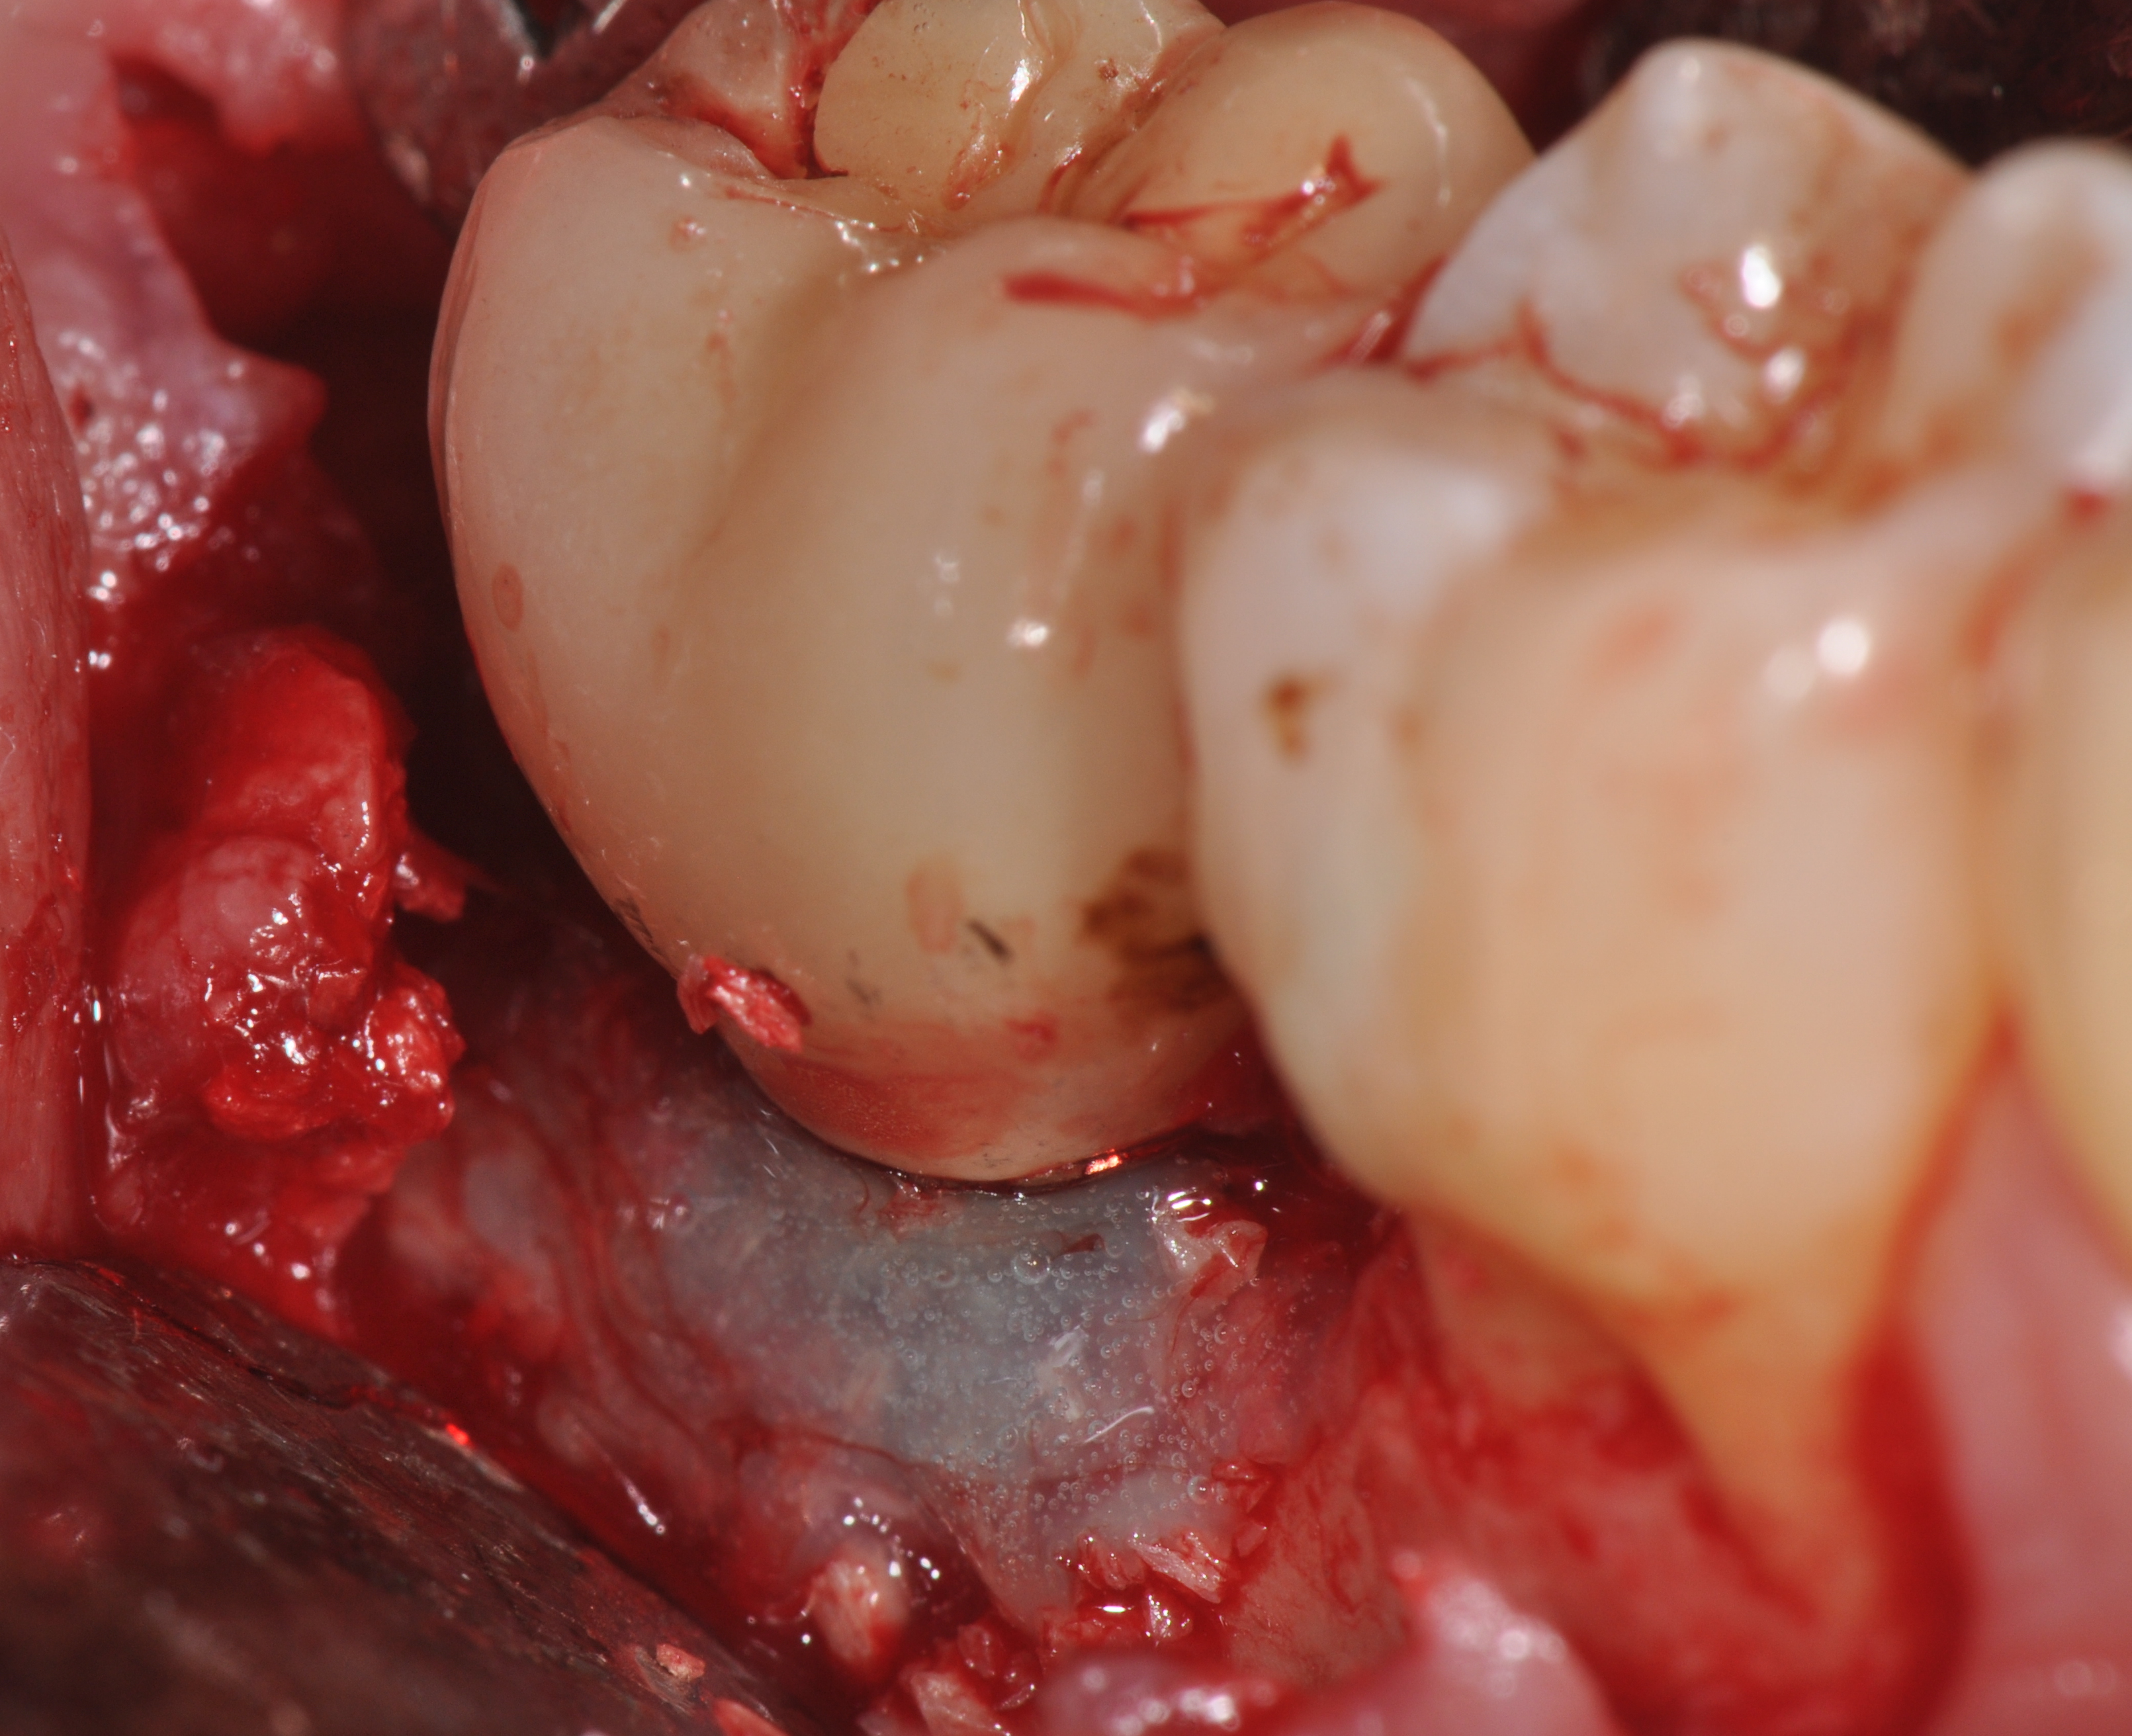

Fig 3. Clinical view of a mandibular left first molar in an 84-year-old patient with a peri-implantitis lesion. The implant had been healthy for the previous 5.5 years.

Figure 3

Fig 4. A radiograph of the area suggests the advanced nature of this lesion.

Figure 4